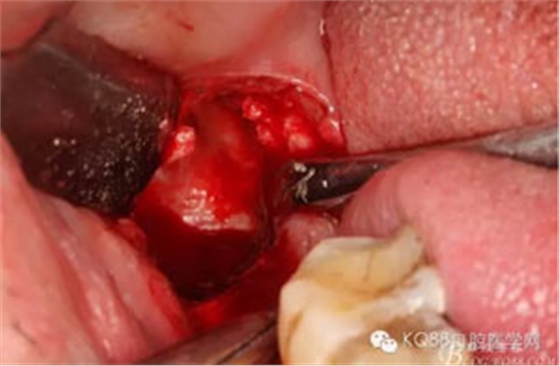

圖6.行角形瓣切開、翻瓣、暴露骨面,可見48牙冠表面有炎性肉芽組織